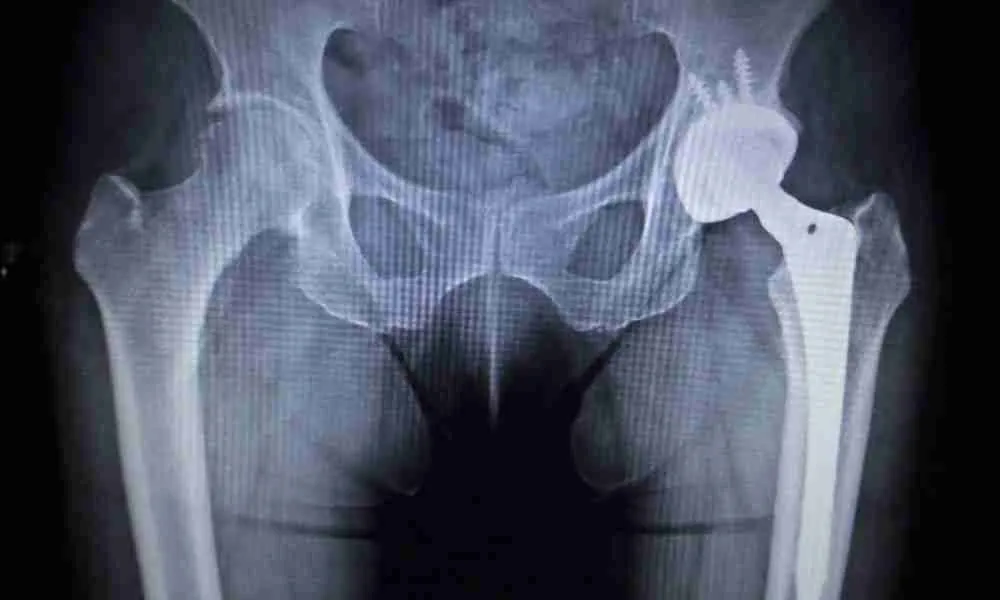

Joint replacements, such as knee, hip, and shoulder implants, have significantly enhanced the lives of individuals suffering from chronic pain and mobility limitations. However, despite their success, recalls do occur. These recalls can be concerning for patients, as they may have implications for both health and well-being. This blog will explain what a recalled joint implant means, why these implants are recalled, how patients are notified, and the steps to take if you find yourself with a recalled implant.

Joint implants are typically made from metal alloys, plastics, or ceramics. Problems like premature wear or corrosion, especially in metal-on-metal implants, can lead to severe complications, including inflammation or toxicity. For example, the ASR hip resurfacing implant was found to have a high failure rate, prompting widespread recalls (Bitar et al., 2021).

Implants are designed to last for many years. However, some may fail earlier than expected, leading to instability or pain. That contributed to recalls of earlier-generation hip replacements (Banerjee & Mont, 2014).